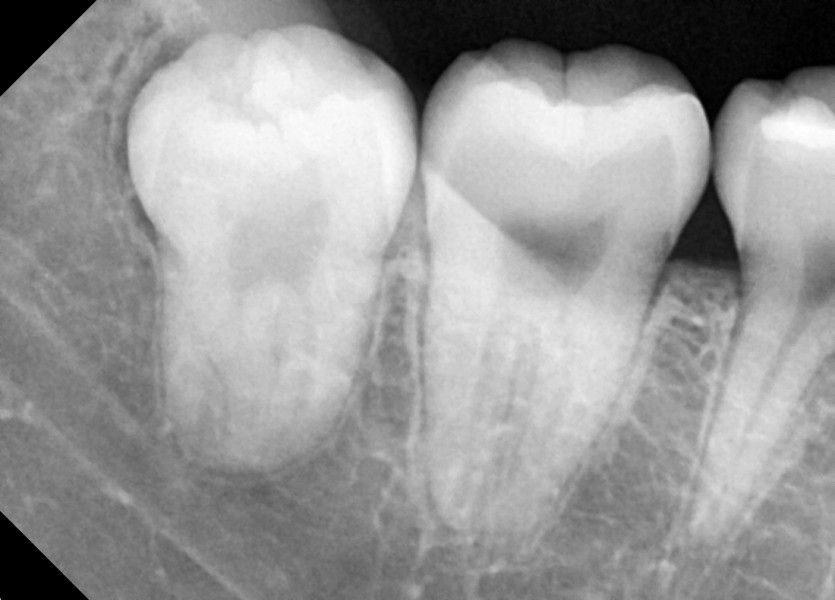

#18,28,38,48 사랑니 발치

구강 외과 전문의가 당일 발치했습니다.